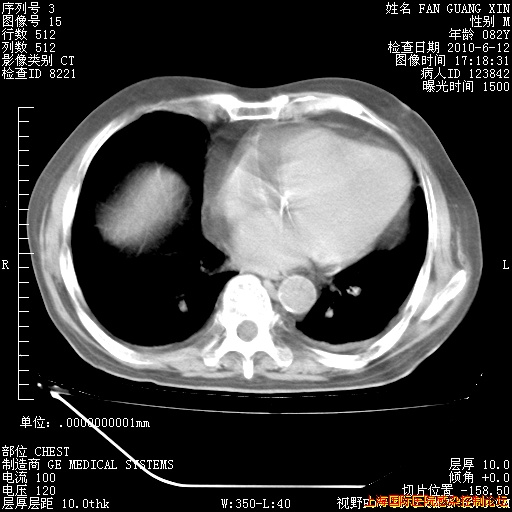

6月12日纵膈窗